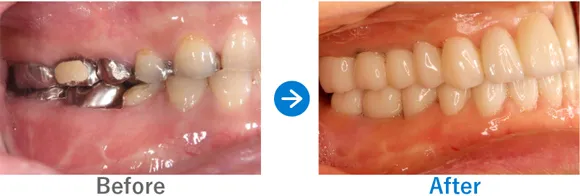

Case8

重度の歯周病で歯並びにも影響が。オールオン4で噛み合わせも改善

残存歯の動揺、義歯の不適合、重度の歯周病

上顎 オールオン4、下顎 オールオン4

7,150,000円(上顎3,575,000円、下顎3,575,000円/内訳:オールオン4(ストローマン)、3Dモデルガイド*、仮歯、セデーション、ボツリヌストキシン注射、3D模型、保証10年)

来院の背景

残っている歯がぐらぐらする感覚があり、使用中の義歯が合わなくなってきているため、インプラントを検討し来院されました。

治療結果

もともと重度の歯周病があり、残っている歯が動いてしまい歯が前に出ているような並びになっていました。そのため、正常な位置で嚙み合わせるように設計し、オールオン4治療を行いました。歯周病に加え喫煙も続けているため、インプラント周囲炎にはとくに注意が必要です。